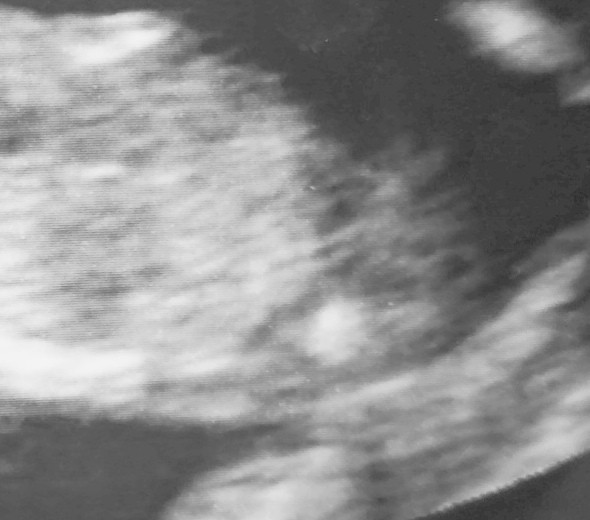

Ja na tym nie widzę tak bardzo wyślij to wczorajsze to Ci zaznaczę gdzie mi się widzialo:D

Ja wiem o które miejsce wczoraj Ci chodziło, bo sama tak myślalam. Ale to było za nisko, tak jakby przedłużenie kręgosłupa 😅 tutaj też mam wrażenie, że w sumie to może nie być nub bo też trochę nisko. Wyżej niż to wczoraj, ale nisko

• IMG_20200603_133458.jpg

IMG_20200603_133458.jpg

313,2 KB · Wyświetleń: 67